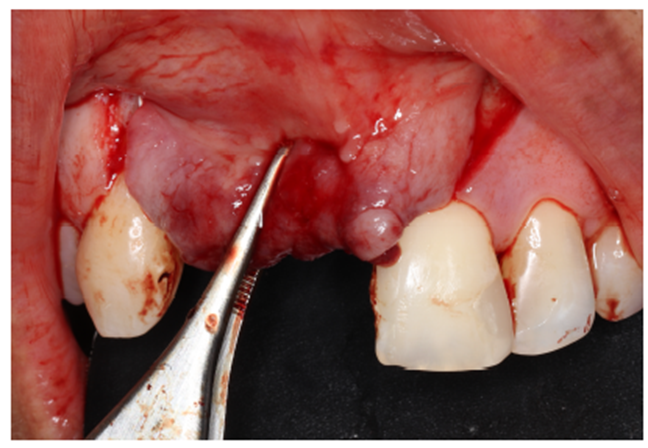

Um dos passos mais importantes dentro da cirurgia de reconstrução maxilar é o fechamento completo da ferida cirúrgica por primeira intenção. Deve-se evitar a qualquer custo a exposição do material de enxerto, pois o mesmo aumenta o risco de infecções. Antes do fechamento completo dos tecidos, é necessário remover quaisquer pontas ativas da membrana, deixando-a com as bordas arredondadas. Com o ganho expressivo do volume ósseo, a escarificação do periósteo é necessária para o relaxamento do tecido, evitando que o mesmo fique tensionado, diminuindo o risco de deiscência de sutura (Figura 9).

Após 75 dias de pós-operatório, foi removida a membrana Cytoplast, onde observou-se ótima neoformação óssea. Apesar do resultado, optou-se por aguardar o período de sete meses para a realização da instalação dos implantes dentários. (Figuras 12 e 13).